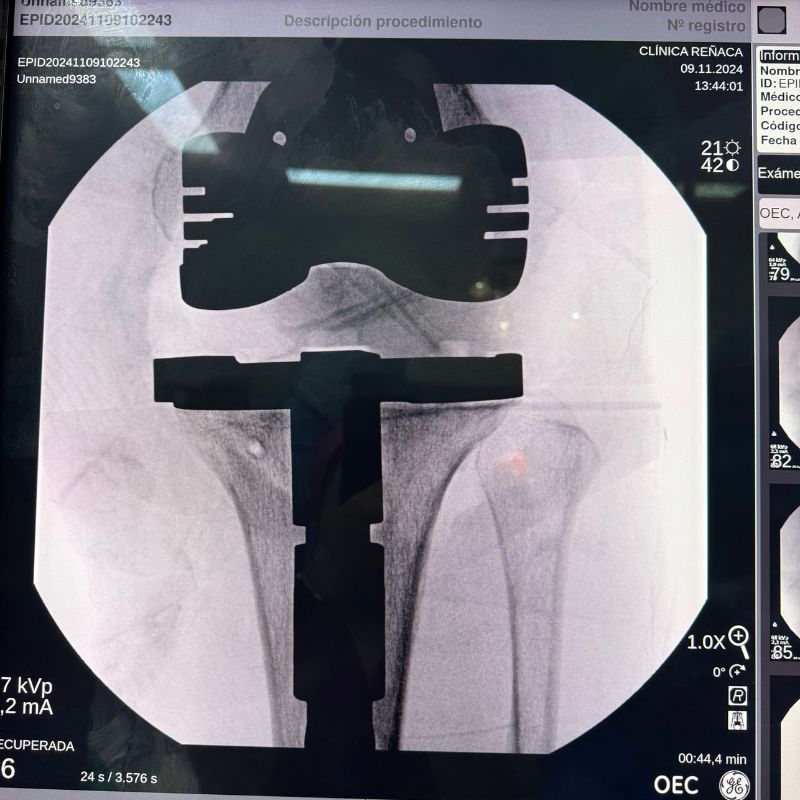

- Prótesis Total de Rodilla.

- Retiro de Prótesis de Rodilla dolorosa o fallida.

- Prótesis de Revisión de Rodilla.